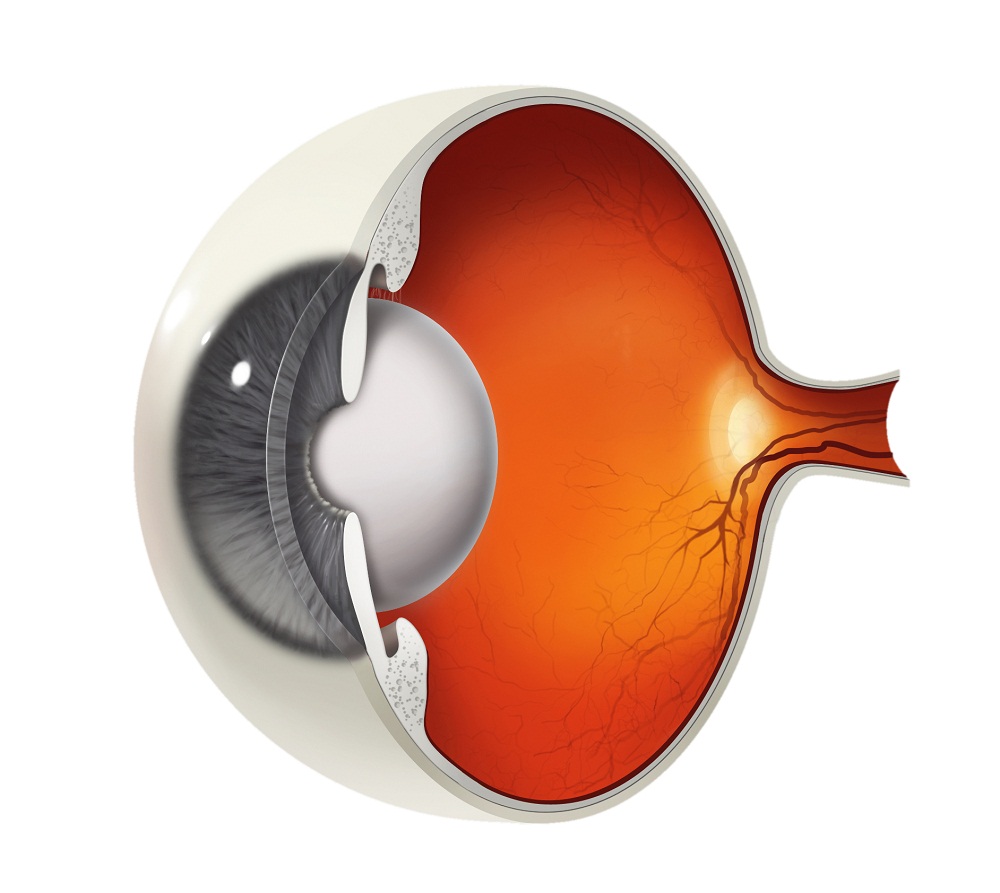

Изображения и анатомия сетчатки глаза

Раздел: Визуальный дайджест